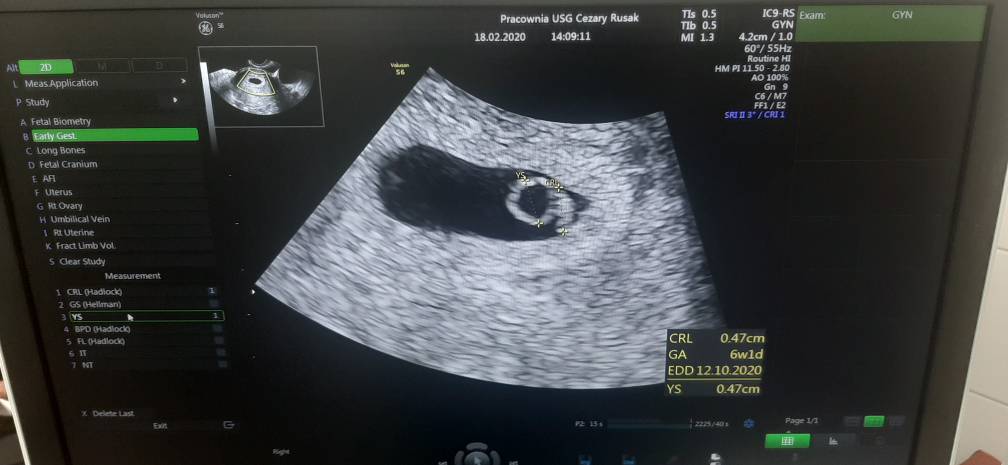

Jestem! W więc tak. Mówi że młodą ciąża więc chyba młodsza. Pojedyncza. Nie dostałam jeszcze karty ciąży. Następna wizyta 10.03 wiecpewnie wtedy założy. Wszytko jest w porządku. Widziałam pikajace serduszko [emoji173][emoji173][emoji173] załączam wam zdjęcie USG.[emoji4]Zobacz załącznik 1082155